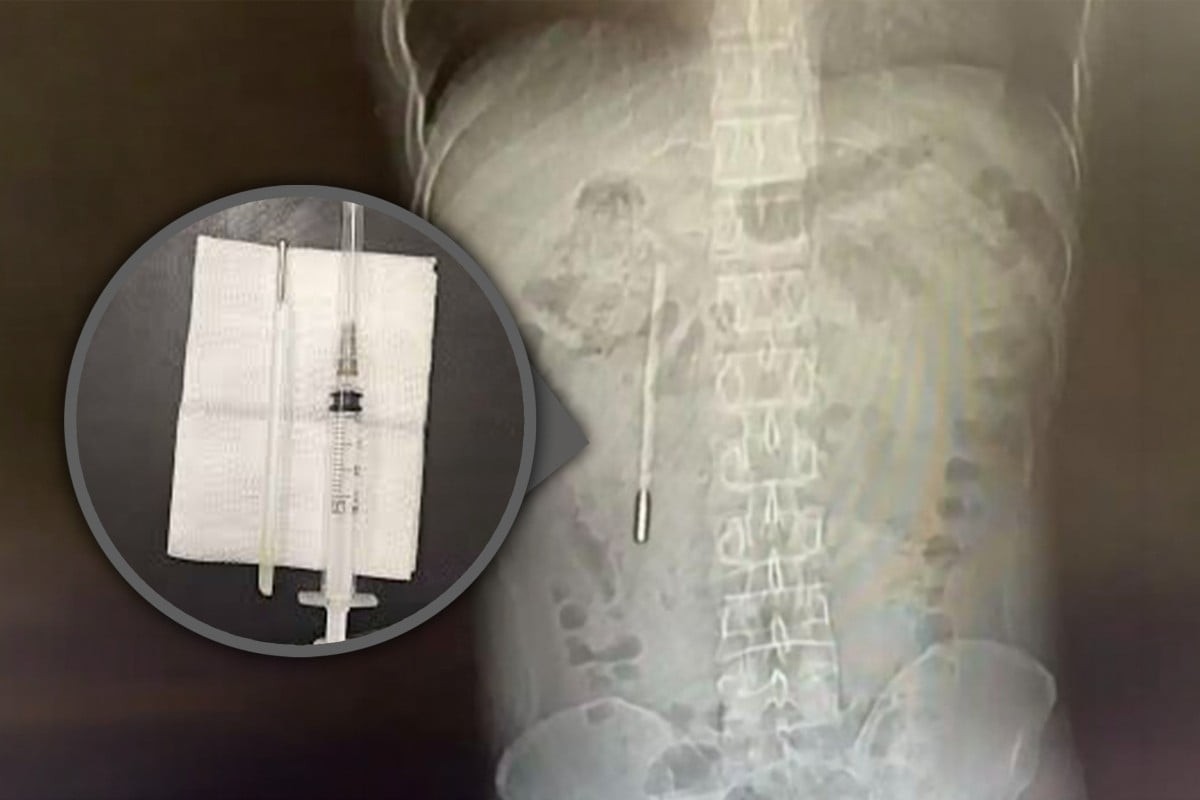

Một người đàn ông họ Vương, 32 tuổi, sống tại thành phố Ôn Châu, tỉnh Chiết Giang, Trung Quốc đã phải nhập viện vì đau bụng. Tại cơ sở Longgang thuộc Bệnh viện trực thuộc số 1 của Đại học Y Ôn Châu, các bác sĩ tiến hành chụp X-quang và phát hiện một dị vật nằm trong tá tràng của bệnh nhân.

Qua kiểm tra hình ảnh, các bác sĩ nghi ngờ đó là một chiếc nhiệt kế thủy ngân. Dị vật này có đầu nhọn đang chèn trực tiếp vào thành ruột, tiềm ẩn nguy cơ thủng ruột và xuất huyết nội nghiêm trọng.

Sau khi xác định tình trạng nguy hiểm, các bác sĩ đã tiến hành phẫu thuật khẩn cấp để lấy dị vật ra khỏi cơ thể bệnh nhân. Ca phẫu thuật diễn ra trong khoảng 20 phút nhưng đòi hỏi độ chính xác cao, do chiếc nhiệt kế nằm gần các ống mật và có thể gây tổn thương nghiêm trọng nếu thao tác không cẩn trọng.

Kết quả, chiếc nhiệt kế được lấy ra nguyên vẹn, tuy nhiên các vạch đo nhiệt độ đã bị mờ sau thời gian dài tồn tại trong cơ thể. Trường hợp này được đánh giá là hiếm gặp khi dị vật có thể tồn tại suốt nhiều năm mà không gây ra biến chứng nghiêm trọng hơn.